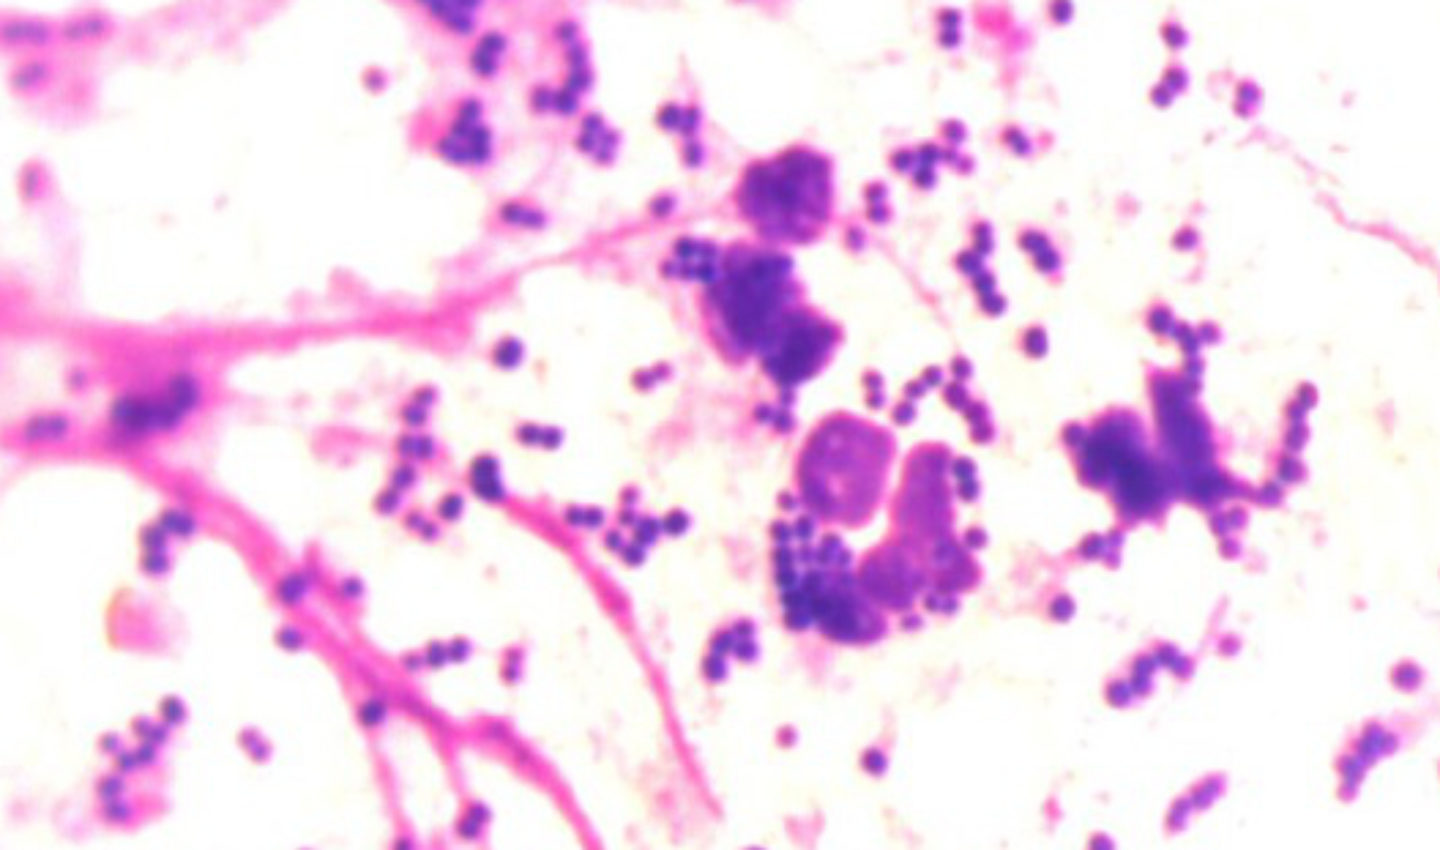

Zwischenzeitlich war der Tupfer unter dem Mikroskop angesehen und es wurden sehr viele Entzündungszellen und Kokken (runde Bakterien) gefunden, eine bakterielle Infektion war in den Ohren!

Weiter wurde Leo in tiefer Inhalationsnarkose untersucht. Während eine Assistentin Leos Narkose überwachte, konnten wir mit dem Videootoskop (Ohrenuntersuchung mit stark vergrößertem Bild auf einem Bildschirm) die Ohren genau betrachten. Zuerst musste dafür der ganze Ausfluss gründlich herausgespült werden. Die gesamte Gehörgangshaut beider Ohren war stark gerötet und den Ausfluss zu entfernen, brauchte etwas Zeit. Solange das Trommelfell (die Trennmembran zwischen äußeren Gehörgang und Mittelohr) nicht sicher gesehen werden kann, muss sehr vorsichtig vorgegangen werden, weil eben in das Mittelohr kein normaler Ohrenreiniger gelangen darf. Während in Leos rechtem Gehörgang nach der Ohrspülung ein reizloses gesundes Trommelfell zu sehen war, zeigte das linke Trommelfell in der Videootoskopie deutlich eine Trübung und ein Loch. Das sind sichere Hinweise auf eine Mittelohrentzündung. Leo hatte uns schon bei der klinischen Untersuchung einen Hinweis gegeben: der trockene rissige Nasenspiegel aufgrund der Reizung eines durch das Mittelohr laufenden Nerves. Nun wurden in Narkose Röntgenbilder von den Ohren (besonders wichtig waren hier die Mittelohren) angefertigt und direkt ausgewertet. Leos Paukenhöhle (das Mittelohr) zeigte noch keine Veränderung im Knochen. Also wurde nun direkt der ganze Eiter aus dem linken Mittelohr sehr vorsichtig mit verträglichen Flüssigkeiten über einen dünnen Schlauch herausgespült und die erste Probe auch wieder unter dem Mikroskop untersucht. Wieder waren Bakterien und Entzündungszellen zu sehen. Um Leo sofort helfen zu können, wurden Medikamente direkt in die Paukenhöhle eingebracht, um dort über mehrere Tage ihre Wirkung zu bringen. Mit einem Schmerzmittel versorgt durfte Leo wach werden.

Leo hat Juckreiz unter dem Bauch (dadurch wurde die Haut im Laufe der Zeit verdickt und dunkel) und an den Pfoten (er schleckt sich sehr viel). Von den braunen Krallen und der Haut zwischen den Zehen haben wir auch einen Tupfer unter dem Mikroskop untersucht und ganz viele Malassezien (Hefepilze) gefunden. Als wir dann auch noch vom Besitzer auf Nachfrage erfuhren, dass Leo ja ab und zu mal ordentliche Blähungen habe, war es fast schon klar: Leo vertrug sein Futter nicht! Nach einer ausführlichen Beratung, welches Futter Leo ab sofort bekommen sollte, konnte es mit Beginn der sogenannten Ausschlussdiät für Leo endlich bergauf gehen- und das ohne Ohrenschmerzen. In der Zwischenzeit war Leo aus der Narkose aufgewacht. Mit einem Shampoo für die Pfoten und den richtigen Medikamenten wurde Leo mit seinen Besitzern nach Hause entlassen.